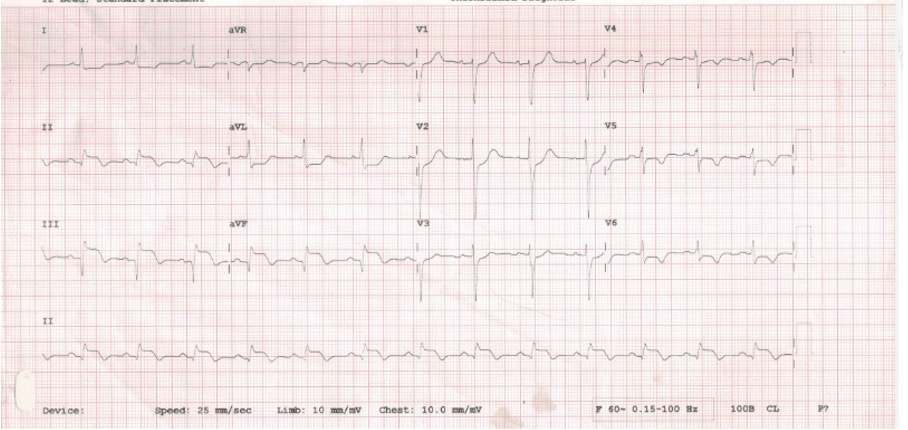

A 68-year-old gentleman with a known history of diabetes mellitus and hypertension had undergone CABG with LIMA to LAD graft in 2019 and now presented with chest discomfort with sweating for 2 days. He was evaluated outside, ECG showed ST and T changes in inferior leads and Echocardiography revealed concentric LVH with hypokinesia of the basal inferior wall.

Coronary angiogram showed patent LIMA to LAD graft mild proximal circumflex disease. The right coronary artery showed proximal 60% calcific stenosis and distal RCA 99% focal calcific lesion with TIMI II distal flow. PCI was attempted but failed due to wire uncrossability of the distal lesion and the inability to deliver devices beyond the proximal lesion. As he had recurrent ACS, he was admitted for PCI of RCA